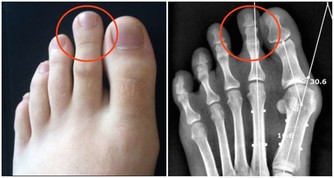

*****3、冠心病*****

根據數據顯示,近年冠心病的年輕趨勢越來越明顯。但是由於早期冠狀動脈粥樣硬化的症狀不明顯,常常會被人所忽視。

殊不知,如若冠狀動脈粥樣斑塊破裂,發生心肌缺血,就會引發致死性心律失常,最終導致猝死。